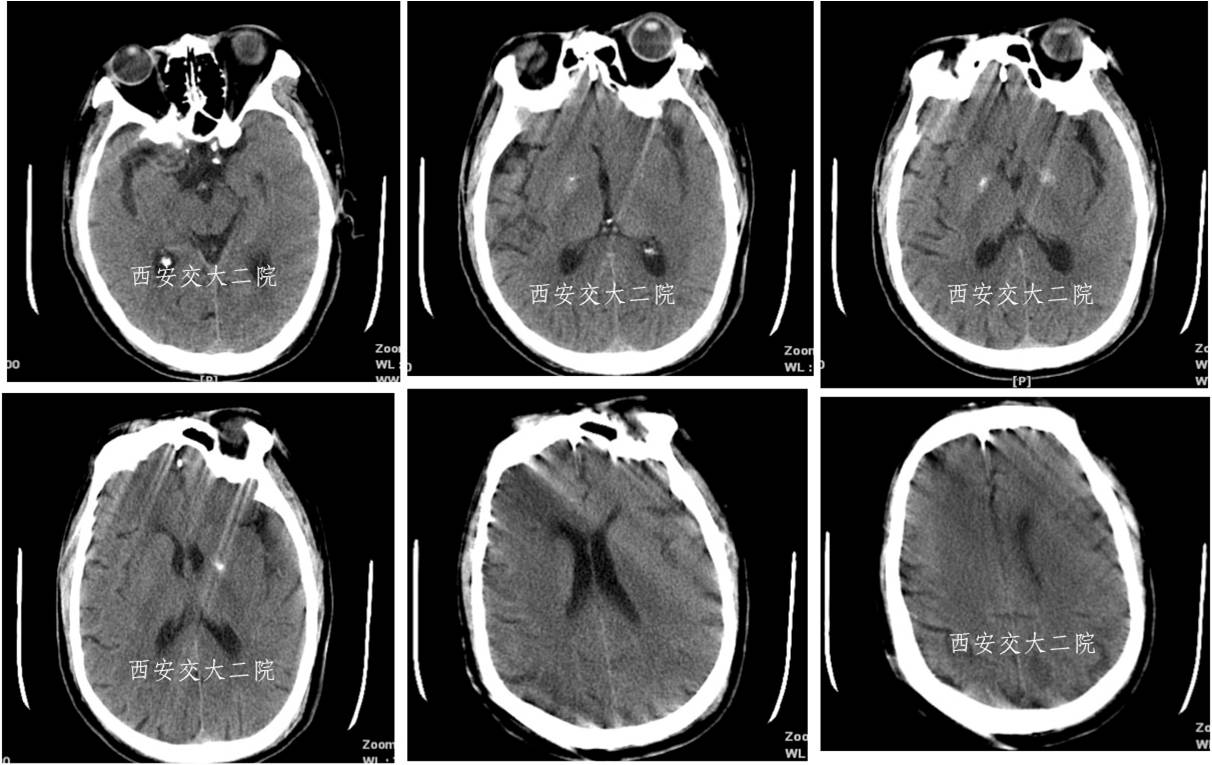

急诊脑CT

病后2小时DSA示左颈内动脉眼段闭塞。

取栓后即刻脑CT及临表

术后24h脑CT及临表

术后4天脑CT及临表

术后2周脑CT及临表